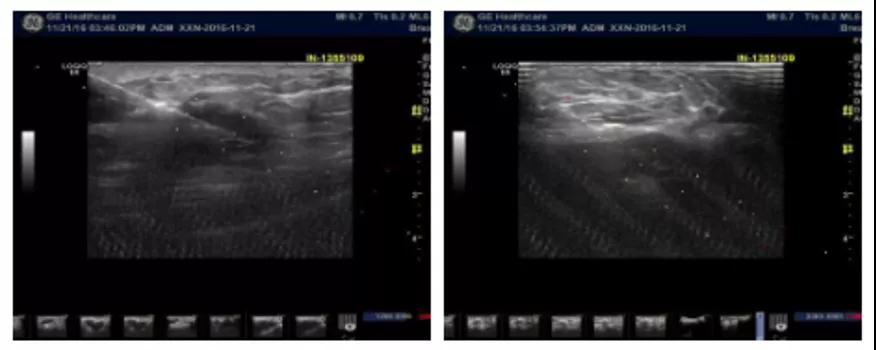

乳腺B超(当地)检查示:右乳实质样团块病灶(BI-RADS-4c级),考虑乳腺癌,右侧腋窝下淋巴结肿大,部分结构已改变。

2016-11-22在超声引导下行“右侧乳腺肿物及腋窝淋巴结穿刺活检术”。

病理示(B201629008):“右侧乳腺穿刺”小块浸润性癌。“右侧腋窝淋巴结穿刺”小块纤维组织及淋巴组织内低分化腺癌浸润。

免疫组化:ER(-)、PR(-)、Cerb-2(3+)、KI-67(+80%)。

入院诊断:右乳浸润性癌ⅡB期(cT2N1M0)HER2过表达型